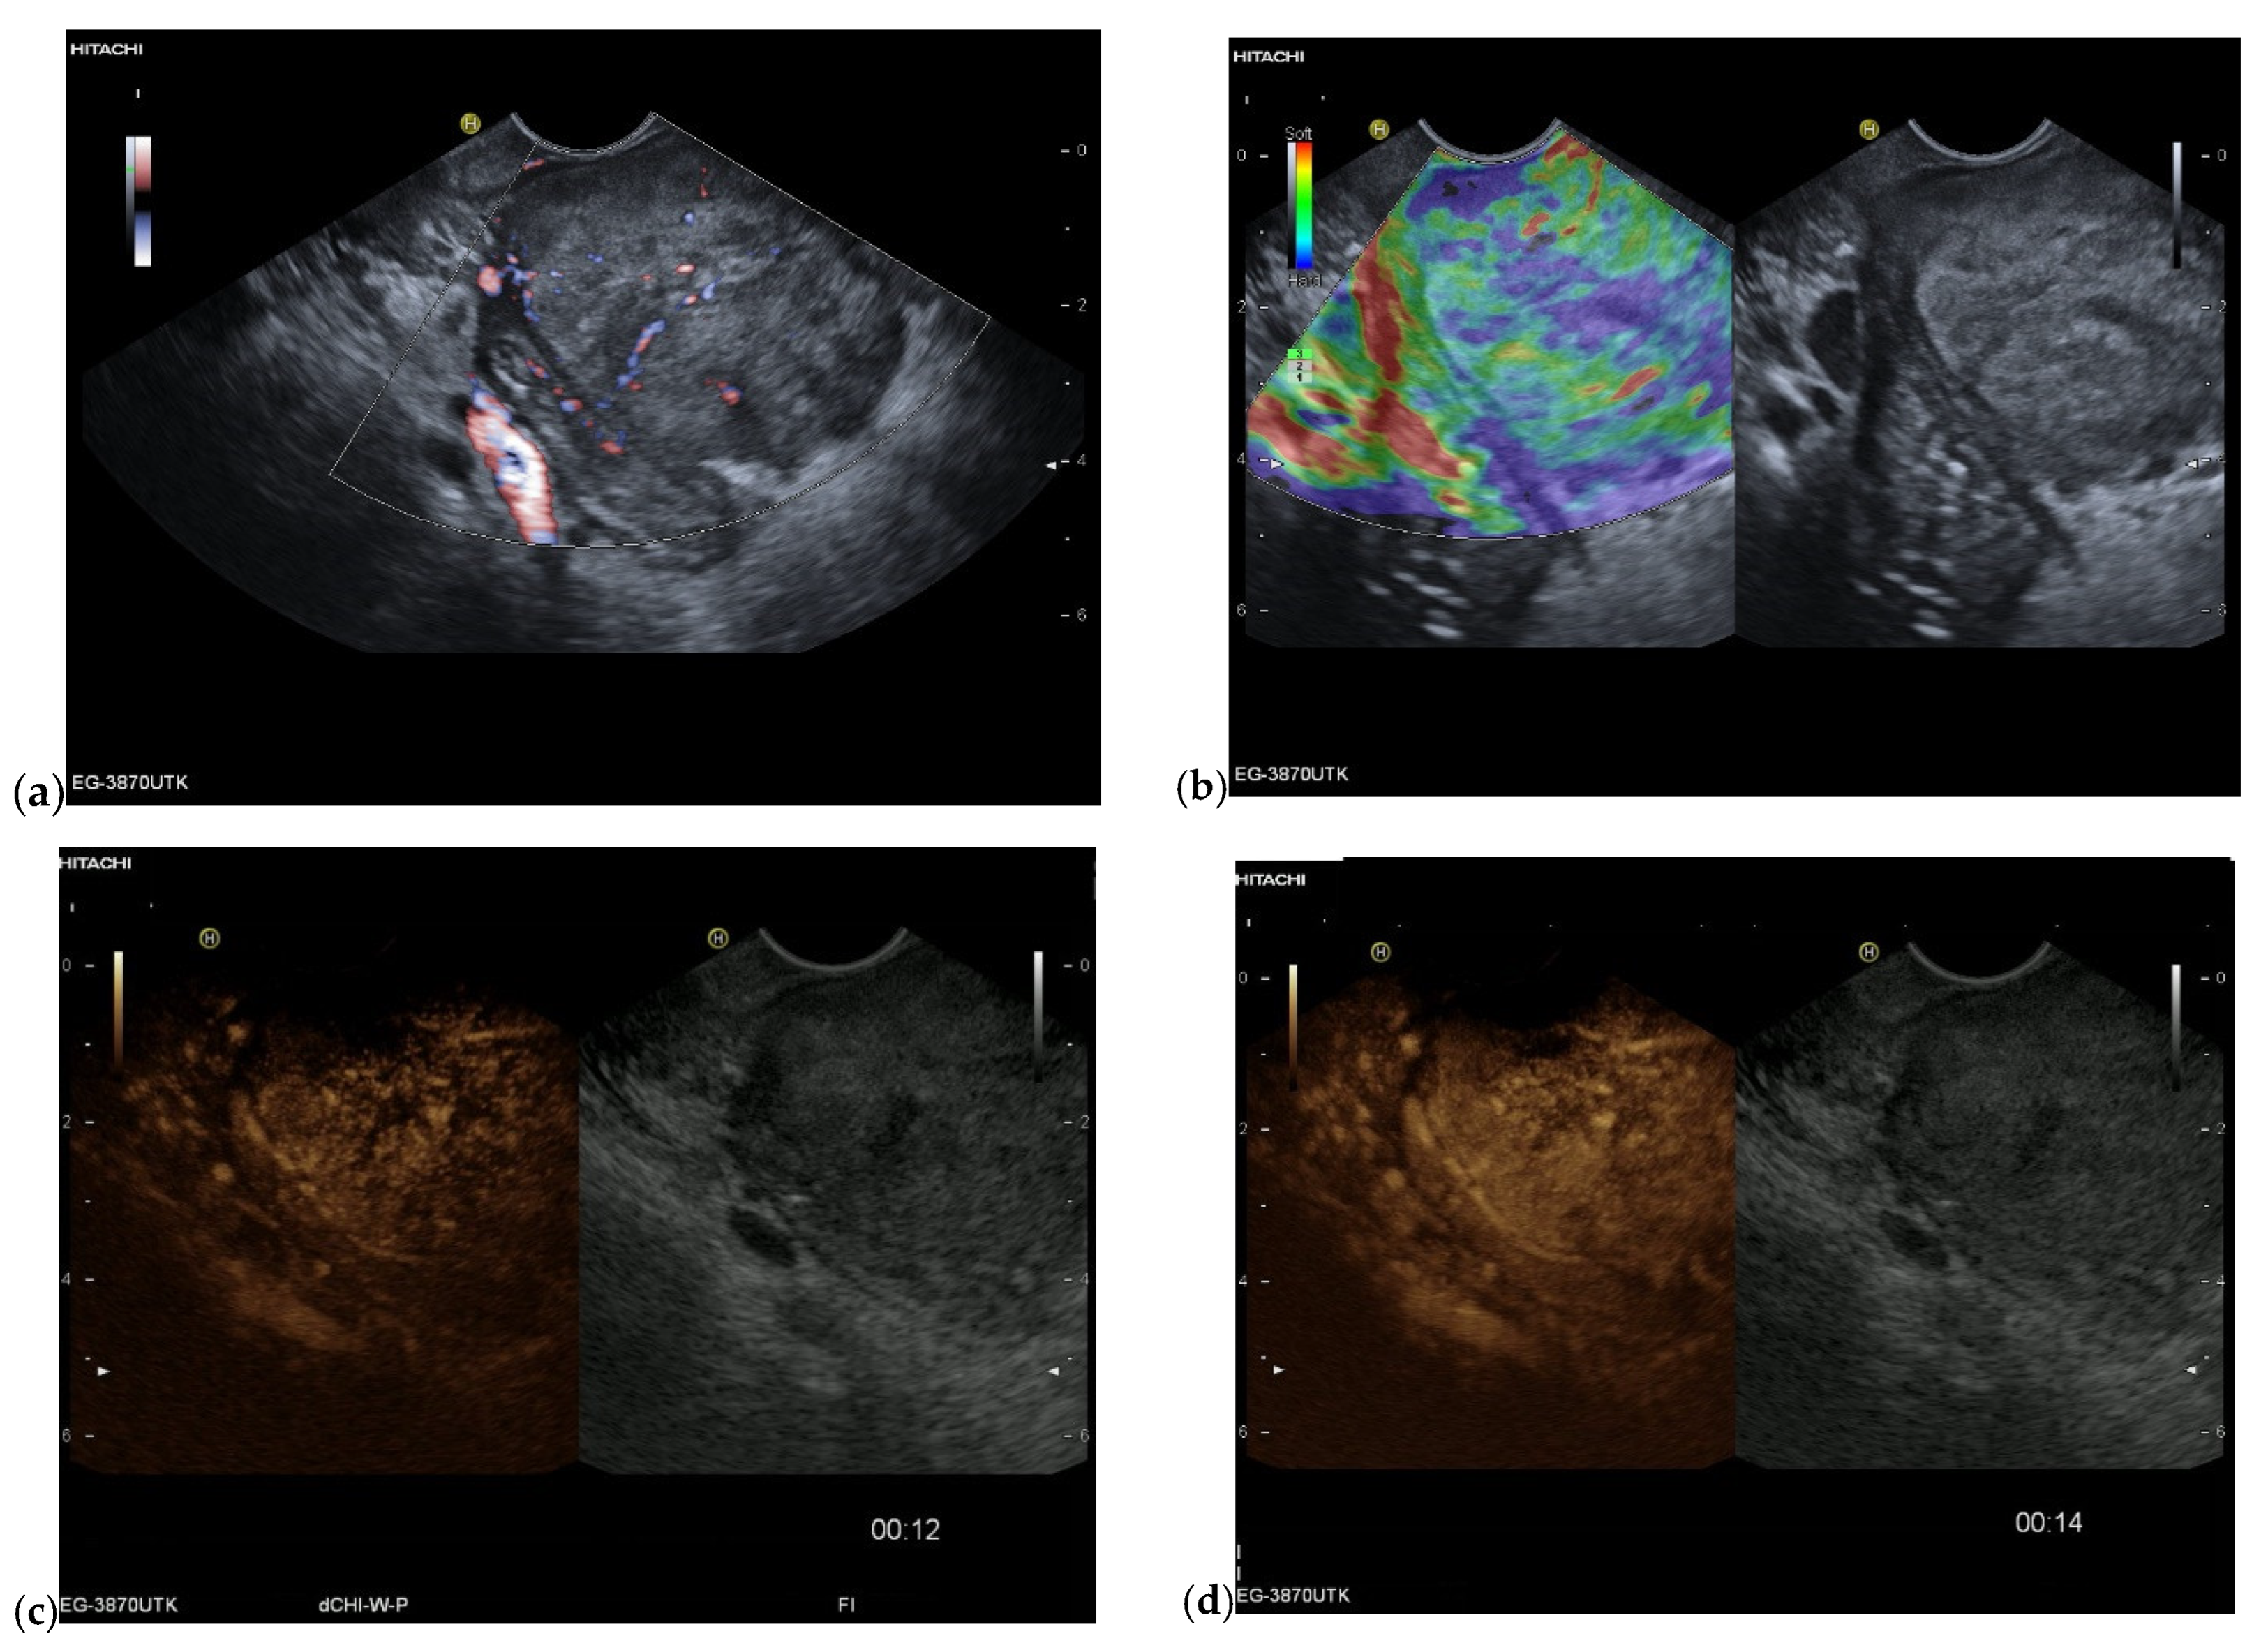

| Colour Doppler Imaging | RCC metastases are hypervascularized Most other pancreatic metastases are hypovascularized | No hypervascularization | Hypervascularized |

| Elastography (small lesions up to 15 mm) [67] | 41% softer or isoelastic, 59% stiffer compared to pancreatic parenchyma | 4% soft or isoelastic, 96% stiffer compared to pancreatic parenchyma | 64% soft or isoelastic, 36% stiffer compared to pancreatic parenchyma |